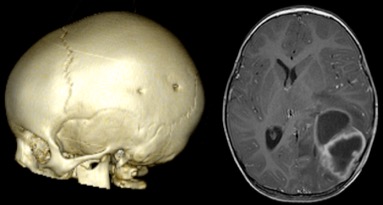

il s’agit d’une urgence très fréquente, dont la banalité ne doit pas laisser méconnaitre les risques

- de plaie pénétrante

c’est la cas en particulier des morsures d’animaux qui peuvent entraîner une plaie durale alors que le point d’entrée est punctiforme.